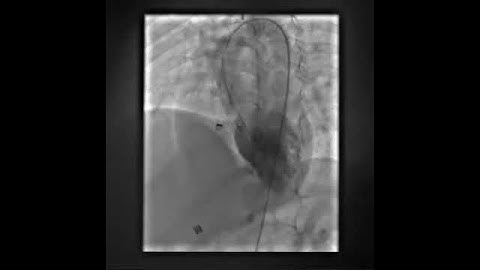

LV Angiogram post device closure of PMVSD